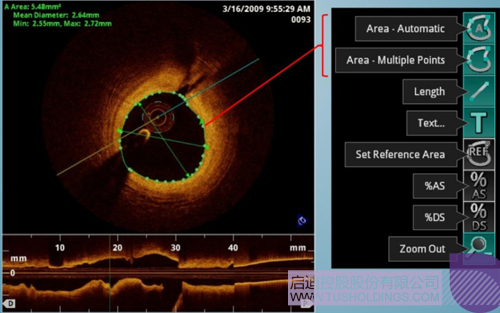

光學相干斷層成像技術(OCT)是一種新型影像技術,它利用弱相干光干涉儀的基本原理,檢測生物組織不同深度層面對入射弱相干光的背向反射或幾次散射信號,通過掃描,可得到生物組織二維或三維結構圖像。OCT由于具有極高的分辨率(10 um),可以對內膜性質和支架結構更加精確地辨別和分析。

在冠脈介入治療迅猛發展的今天,隨著復雜病變患者日益增多,血管內影像扮演了越來越重要的角色。OCT借助其高分辨率的圖像優勢,可以提供更清晰的病變特征和支架植入情況,OCT存在以下優勢:可更精確的檢測介入治療后的血管內情況,如夾層、支架貼壁不良、組織脫垂等,另外,它在管腔直徑和面積方面的測量精度更高。

血管腔內精準評估